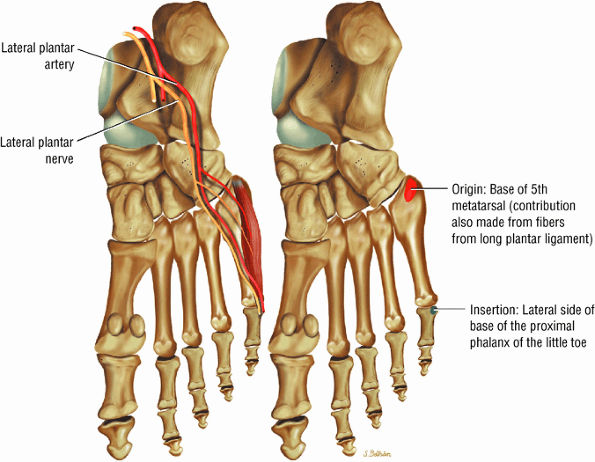

![]() |

FIGURE 5.28 Tibiotalar Joint.

FIGURE 5.29 Impingement.

FIGURE 5.30 Subtalar Facets.

FIGURE 5.31 Tarsal Joints.

FIGURE 5.32 Hindfoot.